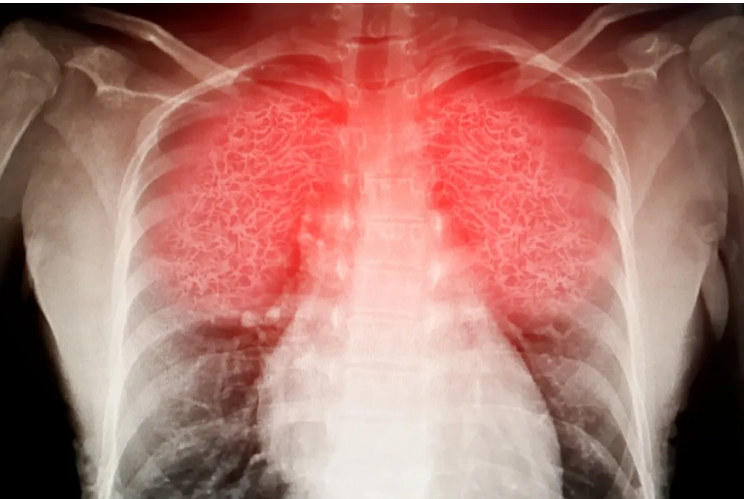

لكن دراسة حديثة حذّرت من أن هذا النشاط قد ينطوي على مخاطر صحية خفية، بعدما اكتشف باحثون نمساويون أن البيئة التي يُمارس فيها قد تحتوي على ملوثات كيميائية ضارة ناتجة عن الأحذية الخاصة المستخدمة فيه، ما قد يؤدي إلى مشاكل تنفسية خطيرة.

وكشف فريق البحث في جامعة فيينا أن أحذية التسلق المستخدمة في الصالات الرياضية المغلقة تطلق أبخرة كيميائية خطرة في الهواء، تحتوي على مركّبات سامة ترتبط بأمراض تنفسية مزمنة وتلف في الأعضاء، بل وبعض أنواع السرطان.

وأرجع الباحثون الخطر إلى النعال المطاطية لأحذية التسلق، والتي تحتوي على مواد مشابهة لتلك المستخدمة في صناعة إطارات السيارات، مثل مركب 6PPD-quinone، المعروف بتسببه في التهابات رئوية وتلف واسع في الأعضاء الحيوية، بحسب تجارب سابقة على الحيوانات. كما تم رصد مادة البنزوثيازول، التي ارتبطت بزيادة احتمالات الإصابة بسرطان المثانة بين العمال الصناعيين.